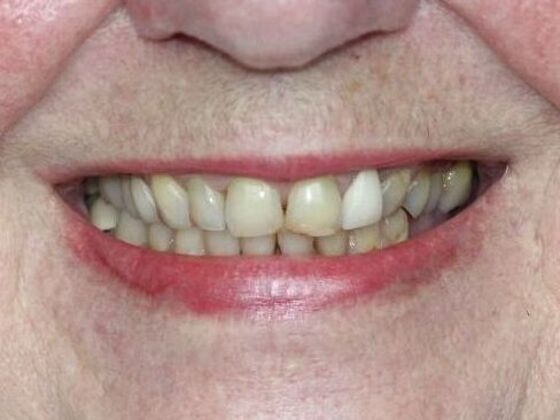

At Lamendola Dentistry, we are committed to exceeding patients' expectations. We offer relaxing amenities and complete continuing education to stay up to date on the latest techniques. Dr. Louie Lamendola is affiliated with prominent dental organizations like the: